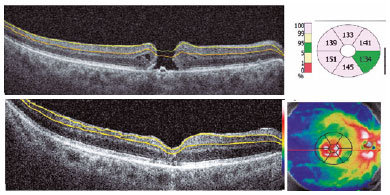

The mean visual acuities at 1 and 3 months after surgery (logMAR 1.2 ± 0.30 and 1.1 ± 0.33, respectively) were unchanged and did not improve, which may be related to other factors rather than the GCC thinning because most eyes did not have good baseline predictive factors and had large macular holes, with long visual loss time and poor anatomical indexes (Table 1). The automatic segmentation performed by the ganglion analysis software of the SD-OCT Revo NX may be altered in eyes where the morphology is distorted by the macular hole (Figure 3). These measurement problems may be the reason for the higher baseline thickness reported and greater initial differences in the mean GCIPL and GCIPL + RNFL thicknesses in our study. A real manual segmentation may be useful for the measurement needed for these analyses.

05-fig03.jpg)